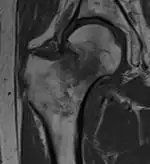

Magnetic resonance imaging (MRI)

Diagnosis of trabecular edema is primarily done via magnetic resonance imaging (MRI). The presence of edema within the bone marrow yields a visible signal on the MRI, due to displacement of the normally fatty tissue within the marrow by interstitial fluid with higher water content; this change in composition is then reflected by the MRI due to differences in the T1-weighted and T2-weighted images.[5][1]

A healthy bone is rich in fat and has lower water content, therefore it appears as bright signals on T1-weighted images and dark on T2-weighted images.[2] Conversely, regions with trabecular edema has lower fat and higher water content. Hence, they have a comparatively lower intensity than normal bone tissues on a T1-weighted image, and a higher intensity on a T2-weighted image.[42]